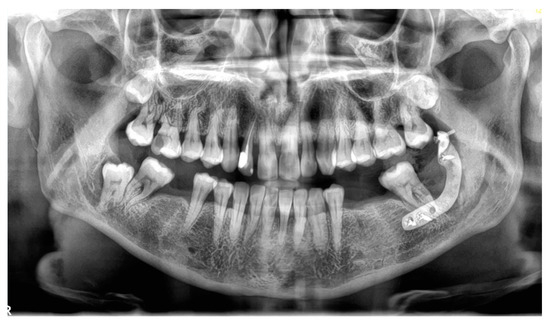

- Fragilized mandibular angle by deep impacted molar, Pell and Gregory class II/IIIC impacted lower third molars [19] associated with pericoronitis or recurrent episodes of osteitis;

2.2. Pre-Surgical Cone Beam Computed Tomography (CBCT)